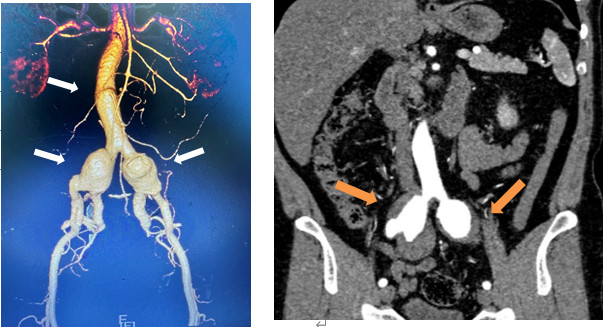

文叔今年53岁,在一个多月前的体检中,意外查出双侧髂动脉扩张。进一步的CT检查提示:双侧髂总动脉及髂内动脉近端动脉瘤,伴附壁血栓形成。这意味着,文叔体内就像埋了随时会爆炸的炸弹:动脉瘤一旦破裂,后果不堪设想。

术前CTA提示腹主动脉局限性瘤样扩张及双髂动脉瘤并附壁血栓(箭头所示)。